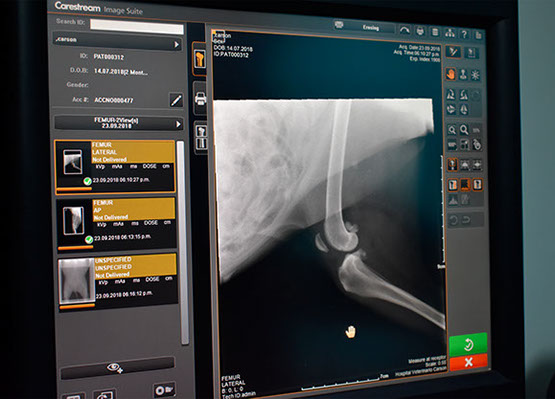

RADIOLOGÍA Y

ULTRASONIDO

Contamos con equipo radiológico digital veterinario para obtener una mucho mejor calidad de imagen y poder así realizar un diagnóstico más acertado en nuestros pacientes, este servicio está disponible las 24hrs y no es necesario realizar cita.

Todas las interpretaciones las realizan médicos veterinarios expertos en el área.